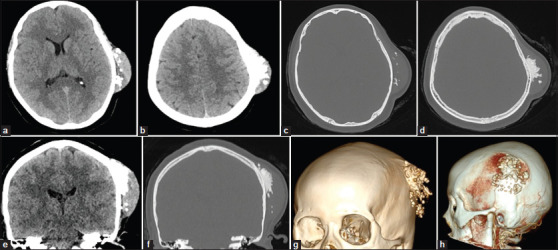

结缔组织增生纤维瘤(DF)是一种罕见的良性骨肿瘤,通常累及面部骨骼,累及颅脑极为罕见。我们报告一个独特的病例DF在一个28岁的妇女的顶骨,值得注意的是其在怀孕期间快速增长的现象,以前没有记录。该病例的影像学特征也与以往报道的所有病例不同。患者接受手术切除,组织病理学证实DF(胶原纤维瘤)的诊断。随访17个月,未见局部复发。我们也提供了32例涉及颅脑DF的病例,分析临床特征、影像学表现、治疗方法和复发模式。本病例强调了在颅脑病变鉴别诊断中考虑DF的重要性,特别是在肿瘤快速生长的孕妇中。为了减少复发的风险,广泛的手术切除仍然是推荐的治疗方法。

Desmoplastic fibroma (DF) is an uncommon benign bone tumor that typically affects the facial bones, with cerebral cranium involvement being extremely rare. We report a unique case of DF in the parietal bone of a 28-year-old woman, notable for its rapid growth during pregnancy-a phenomenon not previously documented. The imaging features of this case also differ from all but one previously reported case. The patient underwent surgical removal, and histopathology confirmed the diagnosis of DF (collagenous fibroma). After 17 months of follow-up, no local recurrence was observed. We also provide a comprehensive review of 32 cases involving DF of the cerebral cranium, analyzing clinical features, imaging findings, treatment methods, and recurrence patterns. This case highlights the importance of considering DF in the differential diagnosis of cranial lesions, particularly in pregnant patients with rapid tumor growth. Complete surgical resection with a wide margin remains the recommended treatment to minimize recurrence risk.